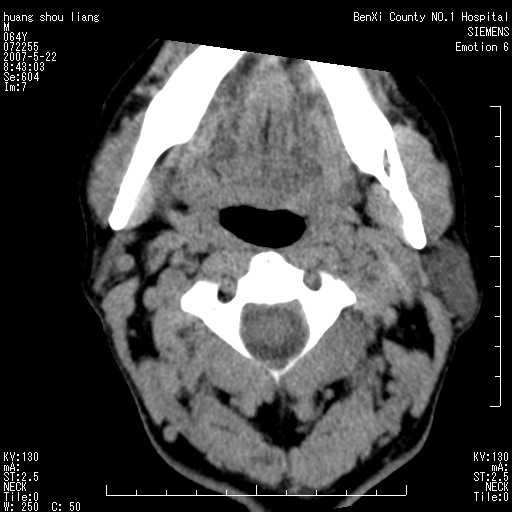

男性,64岁。颈部包块8年。最近增大。

对不起大家,可能是片子发太多有点乱,正常腮腺在下颌角的外侧,颌下腺在下颌体的中部内侧,本例在下颌角内侧偏下,和腺体一点关系都没有,从vrt和mpr上可以很明显看出来,再者肿块是好多粘连在一块的,大家在仔细看看,左侧可能也是吧,我还是考虑为肿大的淋巴结融合在一块,但性质??????

右侧腮腺下部均匀软组织密度肿块,外形不规则,与周围组织分界清晰,考虑右侧腮腺混合瘤或多形性腺瘤。

大家好,病理结果出来了,如大家所说,颌下腺混合瘤。

唉,解剖没学好吧,我诊断错了,不过还是有些不理解回去我在多看看书,谢谢大家的参与,以后我还会奉献好的病例。